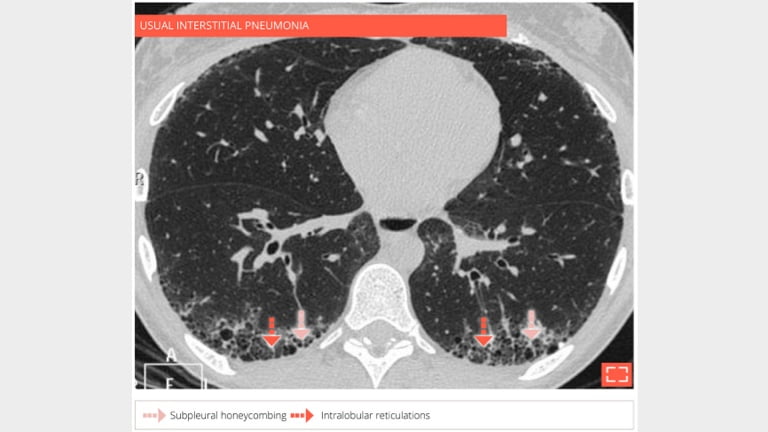

Subpleural honeycombing forming several layers of cysts in a 73-year-old man with usual interstitial pneumonia.

2. Honeycombing

Honeycombing

69-year-old man with usual interstitial pneumonia. Subpleural honey combing is associated with reticular pattern.